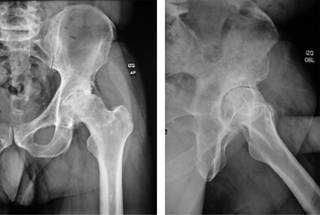

Previa aprobación por los Comités de Investigación y de Ética en Investigación de este hospital (Centro Médico ABC), se efectuó un estudio retrospectivo de todos aquellos casos consecutivos de artroplastía total de cadera, entre Abril de 2018 y Abril de 2020, realizados por abordaje anterior por el mismo cirujano, en el misma institución hospitalaria, igualmente utilizando sistema de reemplazo de cadera con vástago femoral AMIS-H y copa acetabular Versafit-CC (Medacta, Castel San Pietro, Suiza) con liner de polietileno de altos enlaces cruzados y cabeza de cerámica o metal. Se incluyeron 50 caderas en 47 pacientes. Para la totalidad de ellos se formalizó una planificación preoperatoria aprovechando radiografías en proyección anteroposterior con apoyo a una distancia estricta de un metro (Figura 1), proyección anteroposterior de la cadera afectada y proyección oblicua axial a idéntica distancia, así como eje mecánico en la generalidad de los hechos, a excepción de aquellos con fractura de la articulación, a quienes no se les realizó proyección oblicua (Figura 2). Se hizo la medición y selección del tamaño de implantes a utilizar con los sistemas de plantillas específicos de la marca referida. Todos estos afectados tuvieron un seguimiento clínico y radiográfico por 90 días postoperatorios.